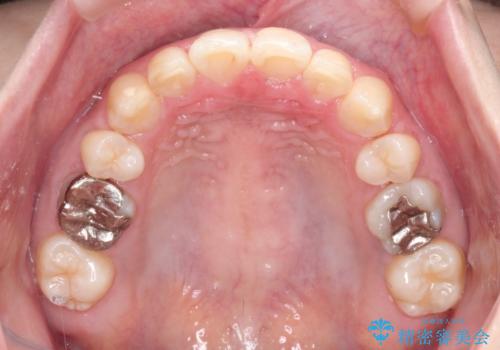

見た目だけではなくかみ合わせも良くなったと満足して頂きました。

治療後は見た目だけでなく、噛みやすくなったと満足していただけました。